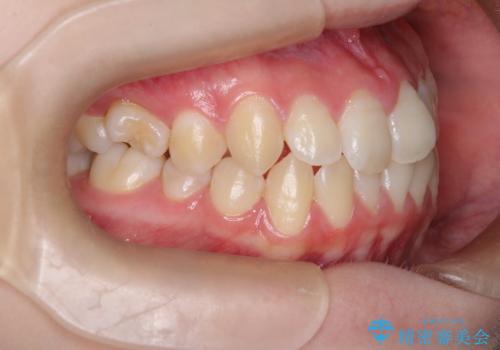

- 患者様は、**前歯の叢生(がたつき)**を気にされて来院されました。

診査の結果、中等度の叢生であったため、インビザラインモデレートでの対応が可能と判断しました。

前歯の叢生は解消され、自然で調和の取れた歯並びが得られました。